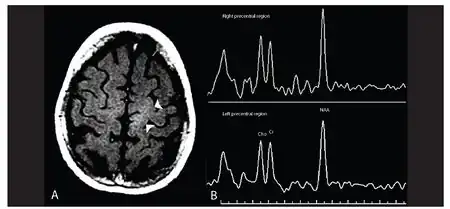

| Primary lateral sclerosis -a)Image shows abnormal hyperintensity in left subcorticol precentral region b) image shows reduced NAA peak and NAA:Cr ratio in the left brain hemisphere | |